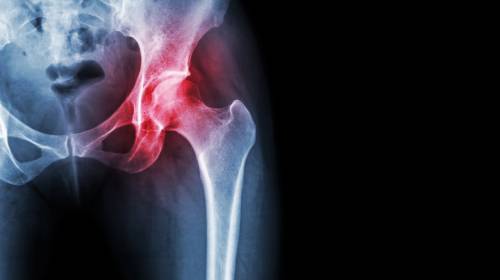

X線篩查對(duì)髖關(guān)節(jié)炎的判斷:

1. 早期影像顯示髖關(guān)節(jié)周圍軟組織腫脹,密度增加,關(guān)節(jié)間隙增寬。

2. 中期影像顯示為關(guān)節(jié)軟骨遭破壞,關(guān)節(jié)間隙變窄,關(guān)節(jié)面骨質(zhì)出現(xiàn)糜爛破壞。

3. 后期影像顯示化膿病變從關(guān)節(jié)囊韌帶附著處入侵骨內(nèi),骨內(nèi)形成膿腫。